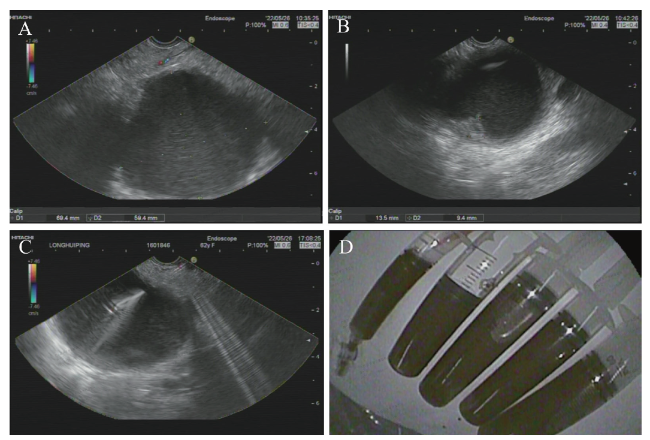

患者入院初步诊断为胰腺肿物性质待查,2022年5月26日于我院行超声内镜(EUS),镜下可见胃底静脉显露,胃体黏膜光滑,胃窦黏膜充血水肿,球部及降段黏膜光滑,十二指肠乳头黏膜未见异常。超声下见胰头、颈体形态规则,内部回声均匀;胰体尾区域见一切面大小69.4 mm×58.4 mm均匀无回声占位,内未见分隔,囊壁稍厚,见一切面大小13.5 mm×9.4 mm稍高回声结节影,与囊壁分界不清,病灶远场强化;主胰管不宽,与占位病变不相通;胆总管未见扩张;彩色多普勒超声显示病灶内未见血流信号;弹性成像显示质软,弹性应变率= 0.72;病灶压迫脾静脉,胃底区域管壁内、外均见不规则血流信号(图2A~C)。拟行细针穿刺活检(FNA),用ECH0-19型超声内镜穿刺针在超声内镜引导下于胃体插入无回声病灶内,抽取出棕褐色液体共110 mL,拉丝实验阴性,分别送常规、血液生化、肿瘤标志物及脱落细胞学检查(图2D)。考虑胰体尾囊性占位:囊腺瘤?假性囊肿?囊液常规:腺苷脱氨酶119.4 U/L(参考值0~20 U/L)。囊液生化:李凡他试验阳性。囊液癌胚抗原767.10 ng/mL(参考值0~15 ng/mL)。囊液穿刺细胞学:见红细胞及少许组织细胞和淋巴细胞,考虑胰腺良性病变。

图2 一例PLEC患者彩色多普勒超声内镜图及抽取的囊液

注:A为胰体尾区域见均匀无回声占位,内未见分隔,囊壁稍厚,见一切面稍高回声结节影,与囊壁分界不清;B为病灶远场强化;C为主胰管不宽,与占位病变不相通,胆总管未见扩张;D为抽取的囊液。